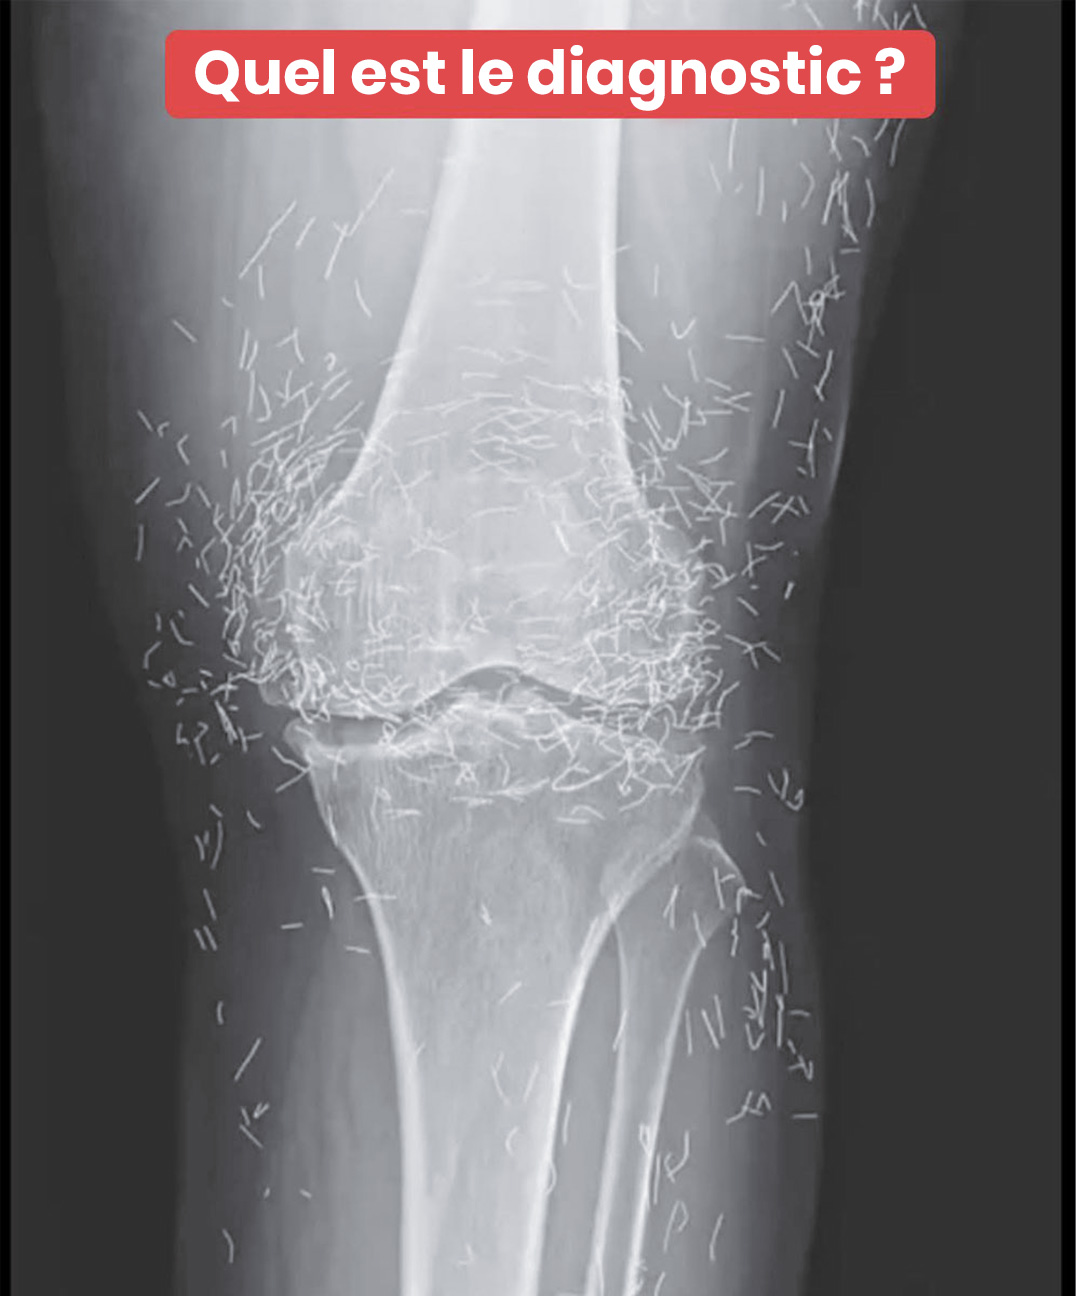

Les genoux d’une femme révèlent, à la radiographie, la présence de centaines d’aiguilles en or

C’est lors d’un examen radiologique de routine que les médecins ont découvert, surpris, des centaines de petites aiguilles brillantes disséminées autour de ses genoux. Une véritable curiosité médicale qui a suscité à la fois étonnement et prudence. Car si l’or est un métal inerte et bien toléré, la présence prolongée d’objets étrangers dans le corps n’est jamais anodine.

D’après des spécialistes en imagerie médicale, ces aiguilles peuvent masquer certaines zones du corps sur une radiographie, rendant plus difficile le diagnostic d’autres problèmes. Et surtout, elles compliquent sérieusement la réalisation d’un examen IRM : le risque que les aiguilles bougent sous l’effet du champ magnétique est réel, ce qui pourrait endommager des tissus sensibles.